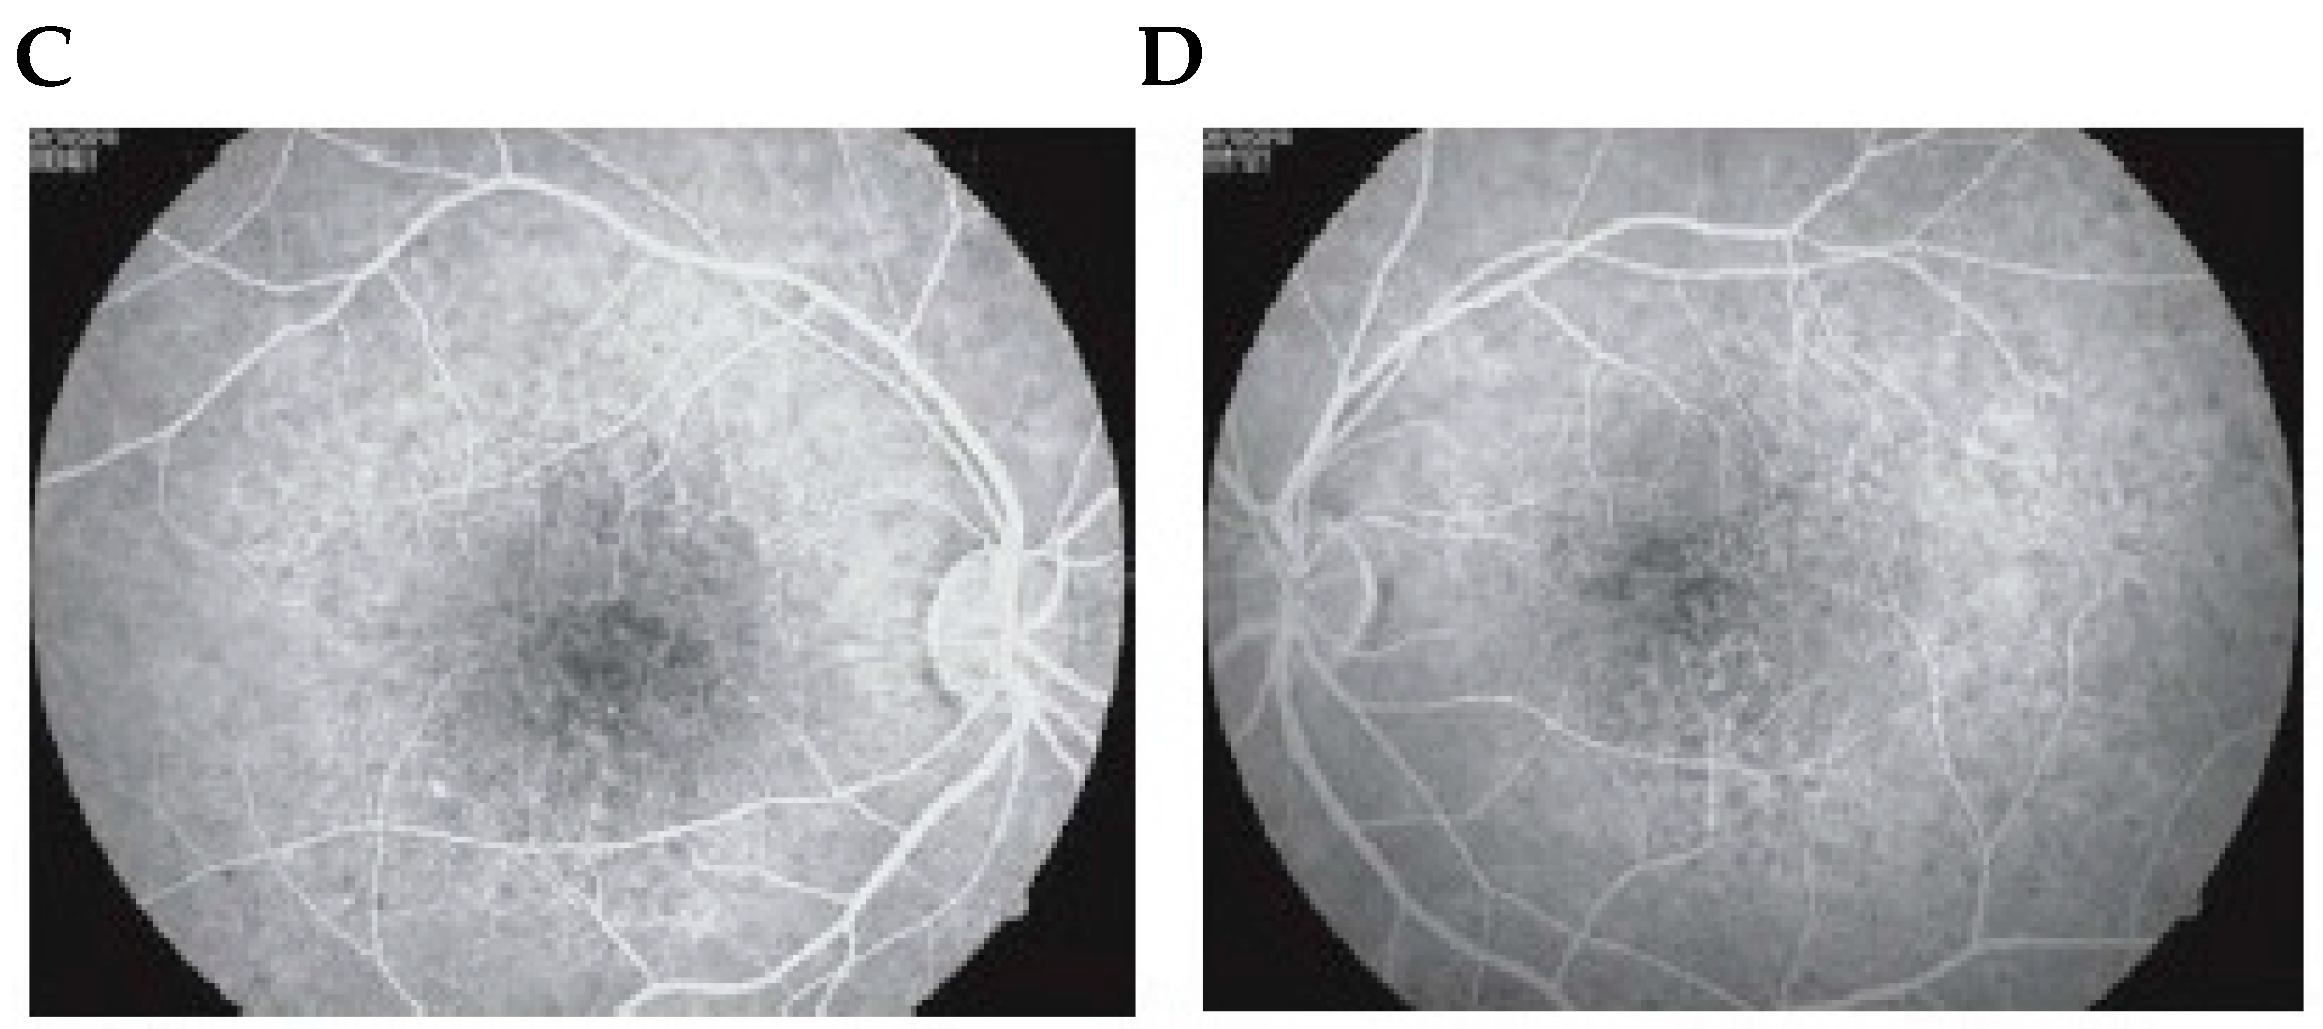

2. Fluorescein Angiography and Indocyanine Green Angiography in Hypertensive Diseases of Pregnancy

2.1. Fluorescein Angiography

2.2. Indocyanine Green Angiography

- Valluri, S.; Adelberg, D.A.; Curtis, R.S.; Olk, R.J. Diagnostic indocyanine green angiography in preeclampsia. Am. J. Ophthalmol. 1996, 122, 672–677. [Google Scholar] [CrossRef]